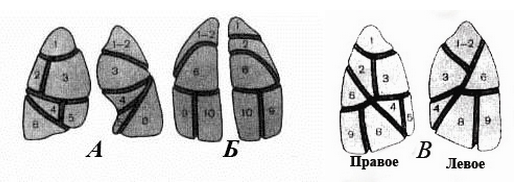

Анатомические изображения сегментов легких различных животных

Раздел: Другие животные